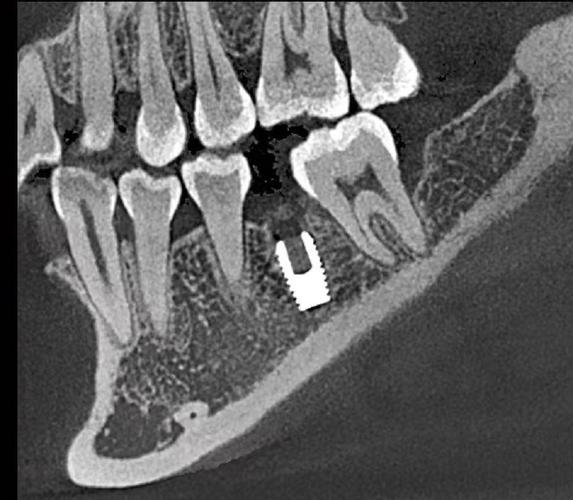

- 现象: 患者口腔内的金属修复体(如金属冠、桥、种植体、金属充填物、牙科合金等)在CT图像上会产生伪影(图像扭曲、模糊、条纹)。

- 影响: 可能干扰对周围骨组织、神经血管结构的清晰观察,影响诊断的准确性,有时需要调整扫描参数或结合其他影像进行综合判断。